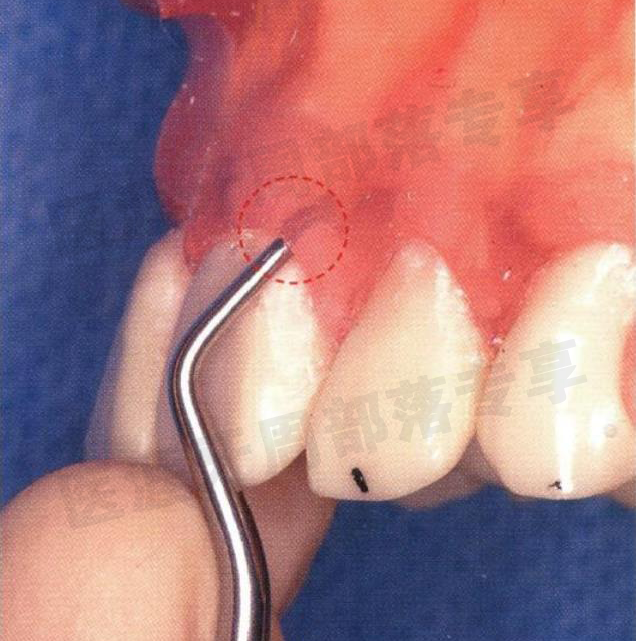

怎么选洁牙器械5个要点带你学习器械洁牙_https://www.jmylbn.com_新闻资讯_第38张

初诊时的牙周精密检查(1997 年11 月) 出血部位较多,局部有较深的牙周袋和排脓。